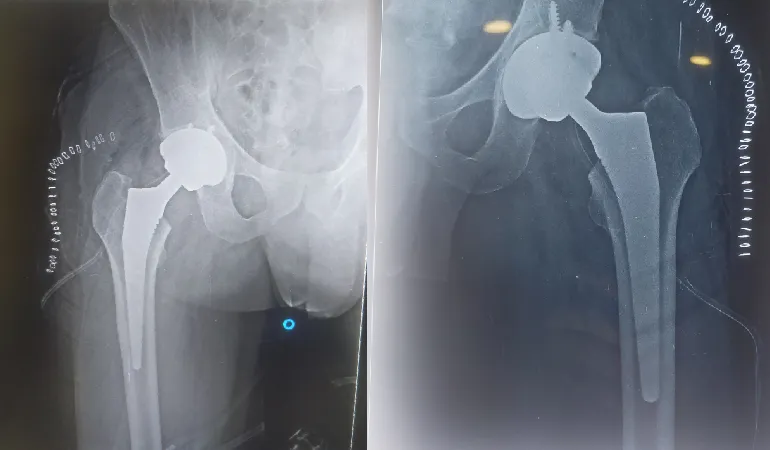

His clinical journey is defined by an extraordinary milestone of performing more than 10,000 successful surgeries. This vast experience ranges from routine fracture care to some of the most complex joint replacements and arthroscopic procedures in the region. Dr. Shah’s practice at Vedant Hospital, Gota, is built on the pillars of precision, ethical practice, and deep-rooted compassion.